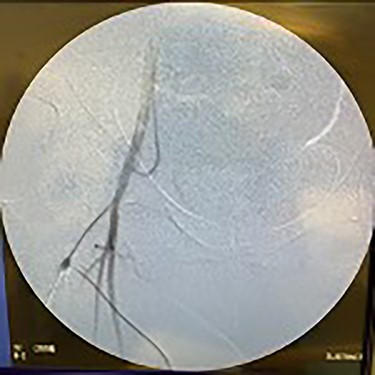

Catheter arteriogram results showed significant occlusion of the left iliac artery (Figs 3 and 4), the right iliac artery (Fig. 1), as well as the distal abdominal aorta (Fig. 2). There were numerous collateral vessels noted, indicating the presence of long-standing proximal stenosis (Fig. 1). The decision was made to use angioplasty to help widen the areas of stenosis. An 8 mm × 40 mm Passeo balloon was advanced from the right femoral artery into the left iliac artery (Fig. 7) and insufflated to 6 mmHg (Fig. 6). The balloon was allowed to remain expanded for 1 min and then was deflated. Next, the distal aorta was repaired in a similar fashion. The balloon was advanced into the distal aorta from the right femoral access and insufflated to 12 mmHg (Fig. 8). The balloon was allowed to remain expanded for 90 s.

Fluoroscopy of bilateral iliac arteries showing significant arterial disease.